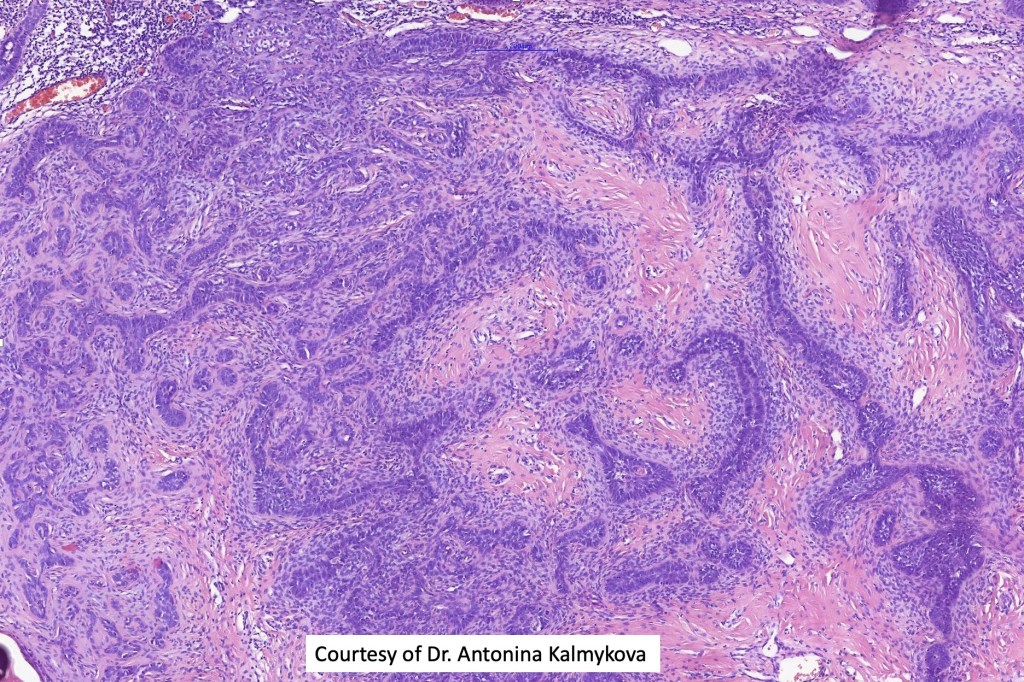

•Biphasic tumors comprising germinative epithelial and mesenchymal components

•Sharply circumscribed nodule, sometimes with a pseudocapsule

•Cribriform and palisaded (rippled) pattern

•Stromal component associated with indentation of epithelial component- follicular mesenchymal bodies (uncommon, more often seen in trichoepithelioma)

•Stromal amyloid often present